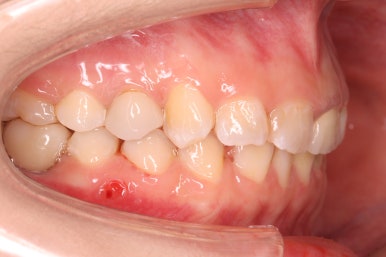

초진 때의 입안 모습입니다.

앞니는 고른 편이였으나 군데군데 틈새가 있었습니다. 약간 삐뚠 모습도 보이지만 환자분께서 개선을 하고자 했던 부분은 아래쪽 어금니 1개가 없는 자리였습니다.

측면에서 본 모습입니다.

자리가 점점 넓어지는 것이 보입니다.